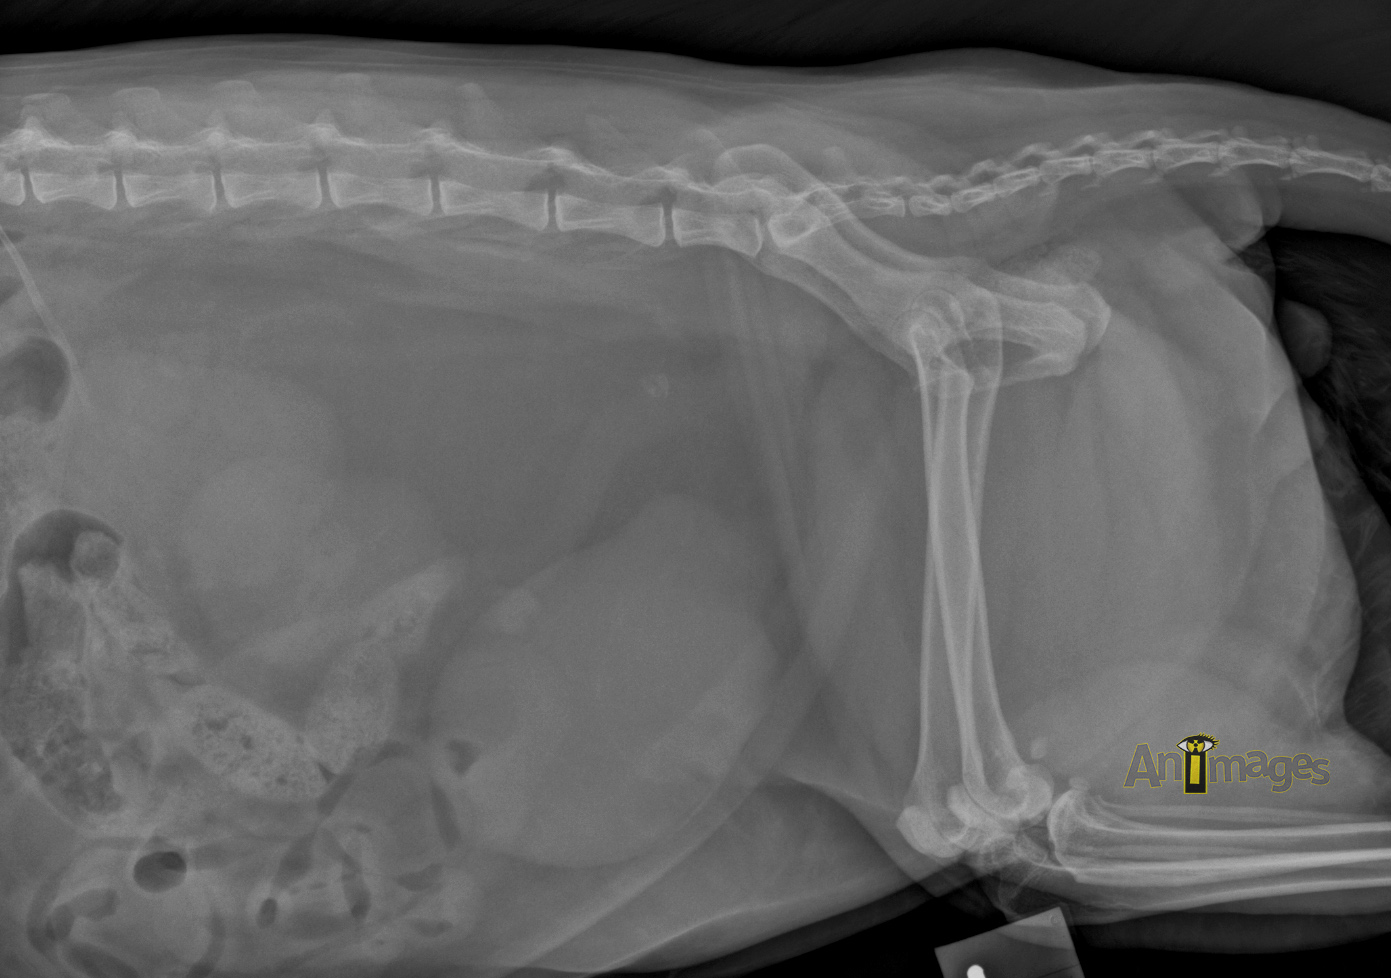

latérale gauche